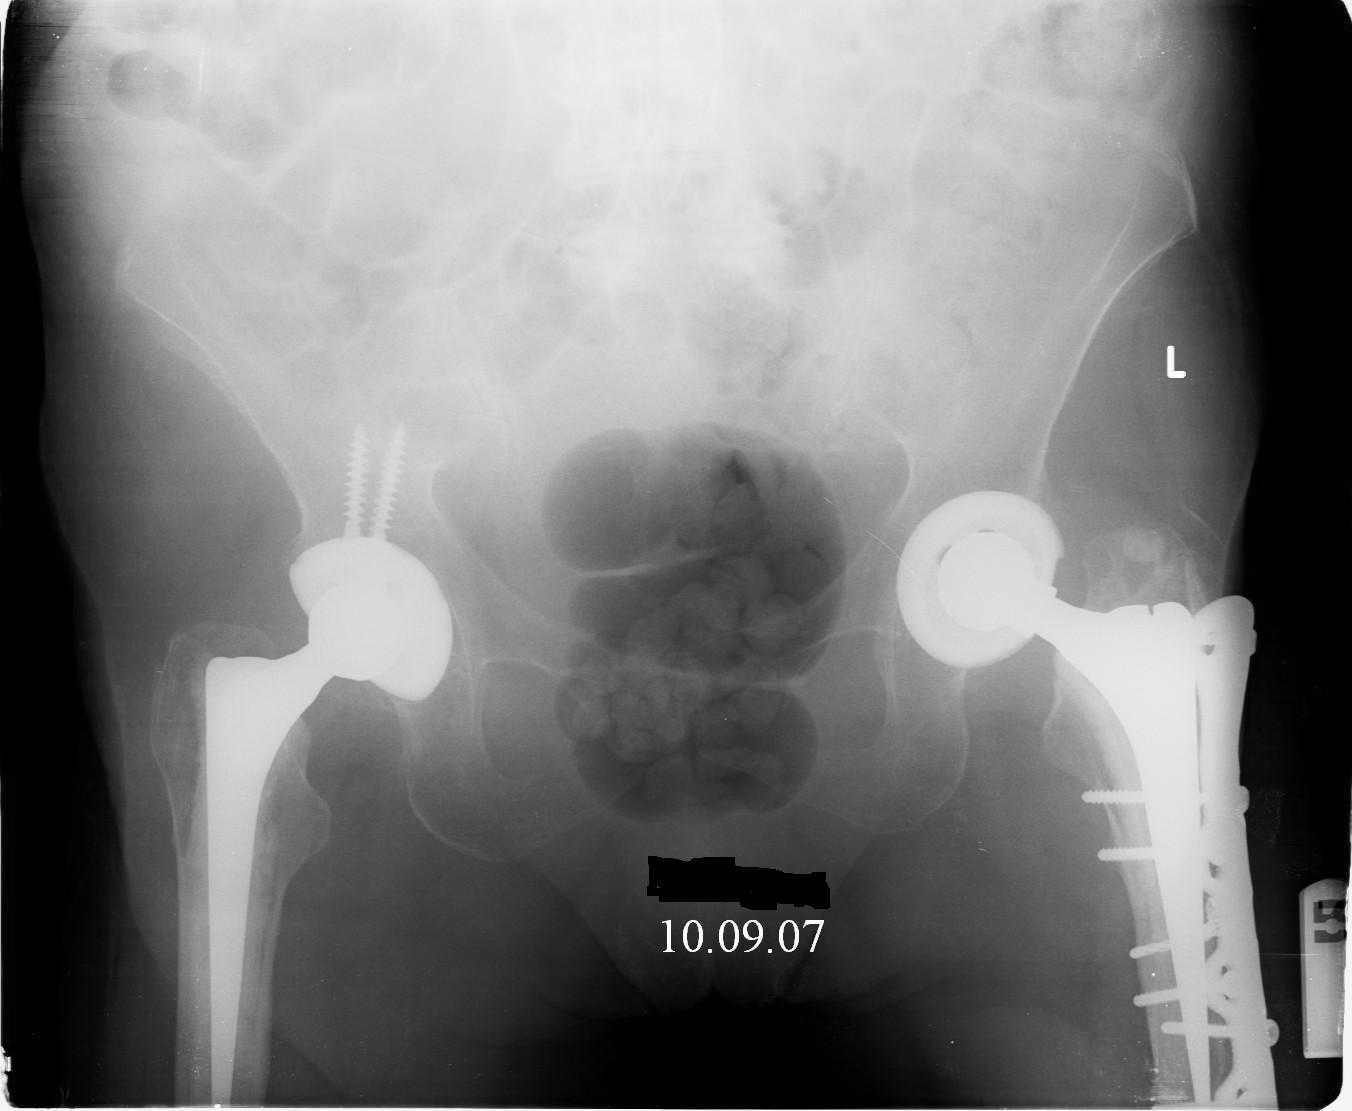

Female, rheumatoid, THA in 2003, car accident in 2006, failed plating. Nailing in Oct 2007. The nail is solid with hollow proximal part where the stem is docked. Last images are in 1 year after

nailing.

Спасибо за обсуждение. После нескольких дней тракции аппаратом сделали. Попытка закрытой репозиции не удалась из-за смещения по ширине, мешали фрагменты цемента. После их удаления репозиция получилась. Еще убрали немного цемента с ножки по латерльной стороне, чтобы обнажить 40-50 мм ее дистальной части, для плотной посадки гвоздя. Дальнейшее введение гвоздя было несложным. Протез показался нам стабильным в проксимальной части как латерально, так и медиально. Картинки в приложении.

THX for the discussion. After few days of traction by ex-fix the surgery was performed. An attempt of closed nailing was unsuccesful because of fragment translation, which was blocked by cement fragments. After removal of broken cement pieces reduction was reached "automagically". Also some cement from lateral part was removed by

chisel to expose distal 40-50 mm of the stem to allow tight fit of the nail. Further fixation by the nail was pretty easy and straightforward. Images attached. The stem looked stable in its proximal part both laterally and medially. Comments/critics are welcome.